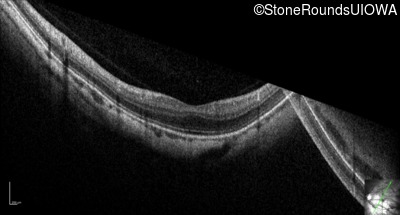

Optical Coherence Tomography - Left - 20/30

Exemplar / OCT Stack

OCT Stack